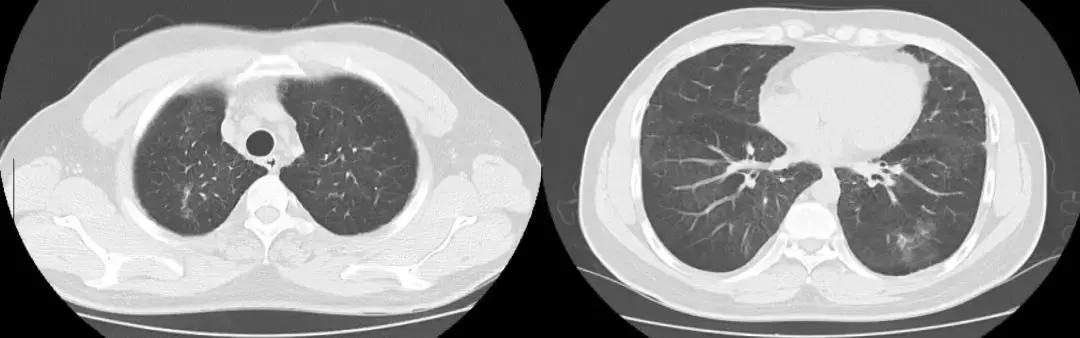

2018-01-22行支气管镜检查:示两侧支气管粘膜充血明显,可见少量白色分泌物,充分吸引;于左下叶生理盐水20ml灌洗2次,回吸收均约10余ml;左上叶、左下叶刷检,刷片共6张。(气管镜报告如下图)。

隆突 右上叶

右中叶 右下叶

左上叶 左下叶